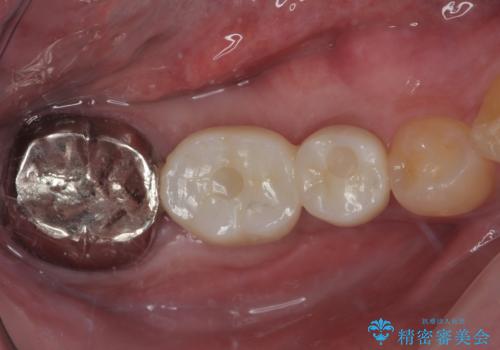

おかげでインプラントは無事に生着し、僅か4ヶ月で治療を終えることができました。